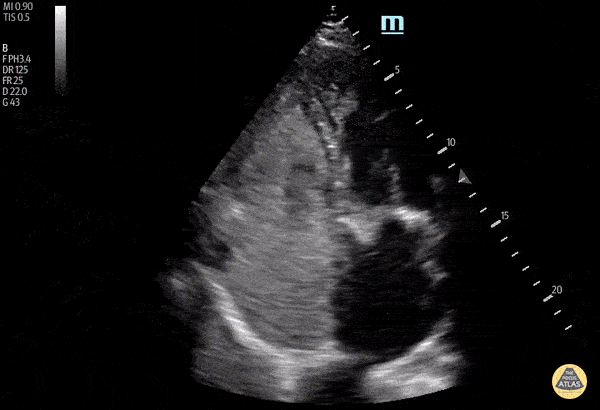

Right Ventricular Dysfunction - Post Traumatic Arrest Echo with RA/RV Thrombus

This image is from a patient presenting after a high speed MVC. The patient had a past medical history of atrial fibrillation and was anti-coagulated. On arrival to ED, the patient was agitated, clammy, and noting shortness of breath. The initial eFAST was negative. The patient was intubated with propofol for CT imaging. 15 min post-intubation the patient became hemodynamically unstable and bradycardic followed by cardiac arrest. An apical four chamber view was obtained during pulse check showing dense clot in RV/RA with minimal cardiac activity. Nishant Cherian Emergency Medicine Registrar